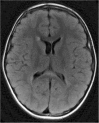

Background and purpose: The splenium of the corpus callosum is the most posterior part of the corpus callosum. Its embryological development, anatomy, vascularization, function, imaging of pathology, possible pathophysiological mechanisms by which pathology may develop and the clinical consequences are discussed.

Methods: A literature-based description is provided on development, anatomy and function. MR and CT images are used to demonstrate pathology. The majority of pathology, known to affect the splenium, and the clinical effects are described in three subsections: (A) limited to the splenium, with elaboration on pathophysiology of reversible splenial lesions, (B) pathology in the cerebral white matter extending into or deriving from the splenium, with special emphasis on tumors, and (C) splenial involvement in generalized conditions affecting the entire brain, with a hypothesis for pathophysiological mechanisms for the different diseases.

Results: The development of the splenium is preceded by the formation of the hippocampal commissure. It is bordered by the falx and the tentorium and is perfused by the anterior and posterior circulation. It contains different caliber axonal fibers and the most compact area of callosal glial cells. These findings may explain the affinity of specific forms of pathology for this region. The fibers interconnect the temporal and occipital regions of both hemispheres reciprocally and are important in language, visuospatial information transfer and behavior. Acquired pathology may lead to changes in consciousness.